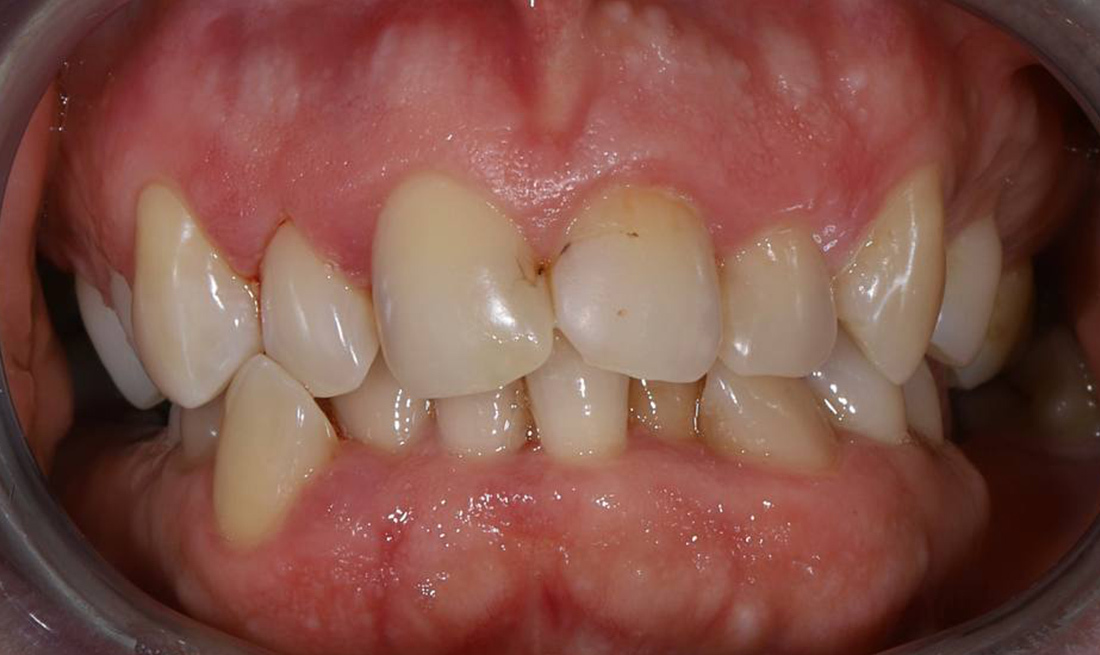

Исправление неправильного прикуса и замена устаревших реставраций для гармоничной улыбки